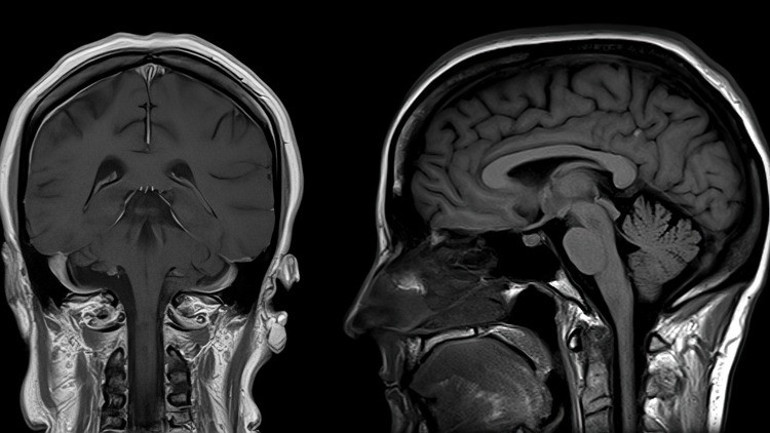

Beyin gri (gri cevher) ve ak maddeden oluşur. Gri madde beynin en önemli işlevlerini yöneten dış katmanında bulunur. Gri madde, çok sayıda hücre gövdesi ve nispeten az sayıda miyelinli akson içermesiyle ak maddeden ayırt edilirken, ak madde nispeten az hücre gövdesi içerir ve esas olarak uzun menzilli miyelinli aksonlardan oluşur. Canlı dokuda, gri madde aslında kılcal kan damarlarından ve nöronal hücre gövdelerinden gelen sarımsı veya pembemsi tonlarla çok açık gri bir renge sahiptir.

Gri madde, beynin nöronal hücre gövdelerinin çoğunu içerir. Gri madde, beynin kas kontrolü ile ilgili bölgelerini ve görme ve duyma, hafıza, duygular, konuşma, karar verme ve kendi kendini kontrol etme gibi duyusal algılarını da kapsar.y

Araştırmanın sonuçlarını yorumlayan Nöroloji Uzmanı Prof. Dr. Dilek Necioğlu Örken, “Bu MR taramaları Covid-19 geçiren kişilerin beyinlerinde belirgin büzülme kalıpları ortaya çıkardı. Kontrol grubu ile karşılaştırıldığında orbitofrontal korteks dediğimiz göz yuvalarının hemen üzerinde yer alan, duygu ve hafıza ile ilgili beyin alanlarından sinyaller alarak karar vermede önemli bir rol oynayan bölgede ve beynin ortasında yer alan ve hafıza ile ilgili bir yapı olan hipokampusu çevreleyen parahipokampal girusta gri madde kalınlığında ve doku kontrastında azalma saptandı” diyor ve ekliyor:

“Çalışmacılar burundaki koku algılayan nöronlardan alınan duyusal bilgiyi birincil koku korteksine götüren yapılarda da doku hasarını ortaya çıkardı. Bir diğer bulgu genel beyin boyutunda da küçülme görülmesiydi. Yapılan testlerde enfekte olmuş katılımcılar ayrıca iki zaman noktası arasında ortalama olarak daha belirgin zihinsel düşüş gösterdi. Beyin kabuğu dediğimiz gri madde bu sayılan alanlarda dikkat, hafıza, dil becerileri ve yürütücü işlevler gibi pek çok yüksek kortikal fonksiyonların işlendiği ve depolandığı alanlardır. Bunların kaybında artış bu işlevlerimizi bozabilir."